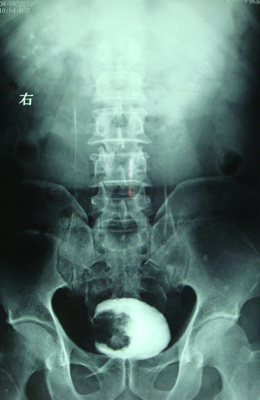

典型病例,男,56岁。无痛性血尿3月。

膀胱占位性病变,呈菜花状生长,考虑膀胱癌。 期待病理。